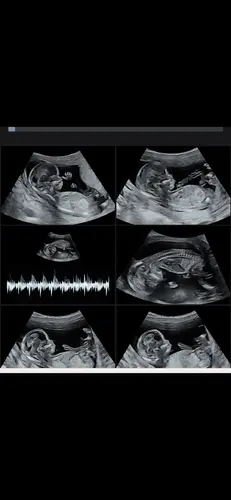

Het is dan met meer zekerheid vast te stellen, maar op basis van de nub-theorie wordt vaak geprobeerd om rond 12–14 weken zwangerschap het geslacht te voorspellen door te kijken naar de hoek van het zogenaamde “nub” (het uitsteeksel waaruit later de geslachtsdelen ontwikkelen):

< 30° t.o.v. de ruggengraat is vaak meisje.

> 30° t.o.v. de ruggengraat is vaak jongen

Ik zie denk ik een jongen

En dat komt doordat het nubje naar mijn idee meer omhoog steekt, maargoed.. dit bied geen officiële garantie 🤭